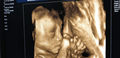

着床出血时间及着床出血和例假的分辨方法详述

受精卵着床大概需要6-7天的样子,这也是着床出血的普遍时间,一般出血会连续3-4天,着床出血的血颜色会比日常经期时候的血色更淡一些,可能还会有恶心、呕吐、腹胀,小便次数的增加,以及对气味的更加敏感和乳房触痛等反应。[1]